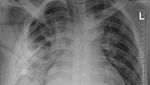

Saat itu, dokter berhasil menutup luka-lukanya dengan jahitan, dan sejak itu ia menjalani kehidupan yang relatif normal, hingga putingnya mulai mengeluarkan nanah. Karena penyebab infeksi tidak jelas, dokter memutuskan melakukan pemeriksaan rontgen. Hasilnya, ada sebuah bilah pisau berukuran besar ternyata tertancap di dalam dada pria tersebut. (Foto: Journal of Surgical Case Reports).

“Pencitraan awal dengan radiografi dada lateral menunjukkan adanya benda logam yang tertahan di bagian tengah toraks, dengan kekeruhan di sekitarnya yang kemungkinan merupakan hematoma terlokalisasi kronis atau yang sudah sembuh, atau fibrosis pascatrauma, yang merupakan sekuel dari luka tusuk pasien,” tulis para dokter. (Foto: Journal of Surgical Case Reports).